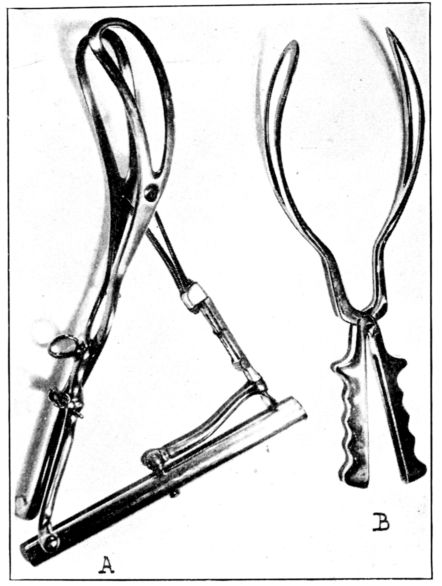

| xxii107. | a. Tarnier forceps, b. Simpson forceps | 301 |

| 108. | Patient in position and draped for forceps operation | 302 |

| 109. | Forceps sheet used in Fig. 108 | 303 |

| 110. | Two types of leggings for obstetrical use | 304 |